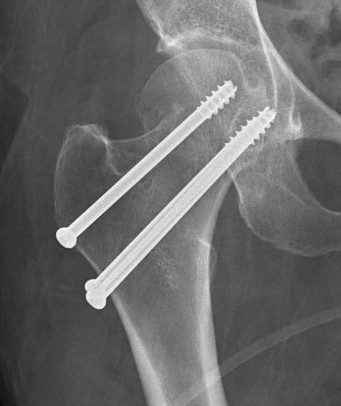

Cannulated screws

Technique

- 3 screws